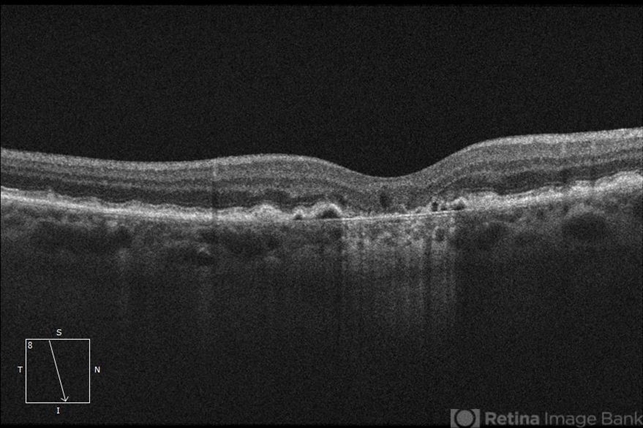

- geographic atrophy, dry age-related macular degeneration (dry AMD), optical coherence tomography (OCT)

- This OCT B-scan shows geographic atrophy (GA) in dry age-related macular degeneration. There is focal atrophy of the RPE and outer retinal layers underneath the fovea, which is typical of GA. The loss of RPE in the affected area, relative to the surrounding macula, results in reverse shadowing within the underlying choroid. This effect is due to more penetration of the optical signal from the OCT illumination source owing to a relative absence of light being reflected as it normally would be from intact RPE. The result is a distinct border on each side of the affected area, where the underlying choroidal signal is more intense than the immediately adjacent areas. Additionally, adjacent to the area of GA are typical drusen, which are nodule-like diffusely hyperreflective accumulations within and under the RPE/Bruch complex, and pigment epithelial detachments (PEDs), which are nodule-like elevations of the RPE with underlying hyporeflective spaces.